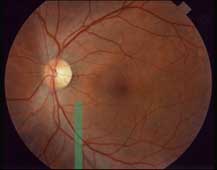

- Štěrbinová lampa - zelený filtr, fixační světlo, poloha štěrbiny je rovnoběžná s osou pozorování, mydriasa

- 60 nebo 90 D čočka - nápis na čočce je čitelný ze strany pacienta

- Trpělivost - výpadek je tmavší barvy, bez žíhání, cévy jsou ostře ohraničené.

Neporušená místa jsou světlejší a mají jemné žíhání přesahující i cévy. Poškozená místa jsou tmavší, bez žíhání a cévy jsou jakoby obnaženy.